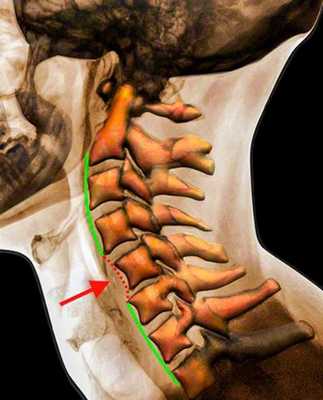

Травма шейного отдела позвоночника

Рентгенограмма. Подвывих в шейном отделе позвоночника. Цветовая обработка изображения.